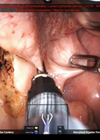

Robotic head and neck surgery: current state of the art and future innovations

Technology and innovation has provided modern head and neck surgeons with successive generations of robotic surgical systems, fibre-optic lasers, and novel tools which have ushered in a new era of minimally invasive surgery for tumours of the pharynx and larynx....